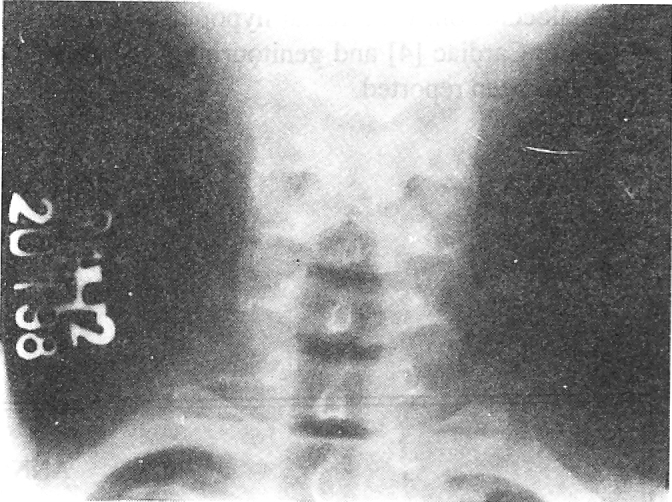

Fig. 2.

Radiogram of cervical spine showing bifid C-5 vertebra.

An 18-year-old boy presented to the OPD of this hospital with mass in left eye and skin tags in front of left ear since birth. The condition was constant since birth. No family history of similar defects was present. Clinical examination revealed an Epibulbar Dermoid in left eye and two preauricular appendages in front of left ear (Fig-1). The eyeballs and ears were normal in all other respects. X-Ray of cervical spine revealed spina bifida of C-5 & C-6 vertebrae. There was no neurological deficit. (Fig-2). Excision of epibulbar dermoid and preauricular appendages was done under local anaesthesia in a combined effort by the Eye and ENT specialists. Histopathology report confirmed the clinical diagnosis (Fig-3).

Involvement of axial skeleton (vertebrae and ribs) has been observed in 24% of the patients in the largest series reported by Rollnic et al [3]. Spina bifida is the commonest and least severe of all anomalies. Hemivertebra, loss of vertebral arch and fusion of posterior elements of cervical vertebrae have also been reported.